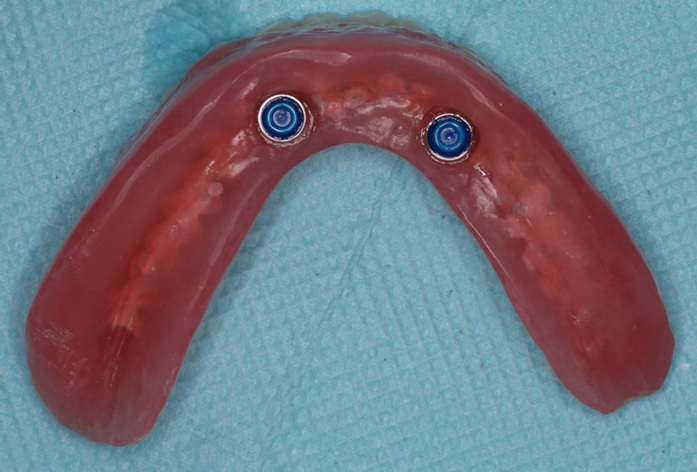

在10年前甚至更早的时候,当全口牙都缺失后,我们较多采用种植体支持的覆盖义齿。这种方式需要每天将义齿取下清洁。回顾世界范围内的多项研究,发现种植体支持的覆盖义齿5年成功率为24.8%-100%。当上颌2颗种植体支持覆盖义齿时,5年成功率仅为24.8%。

下颌2颗种植体,为覆盖义齿提供固位

种植支持覆盖义齿修复